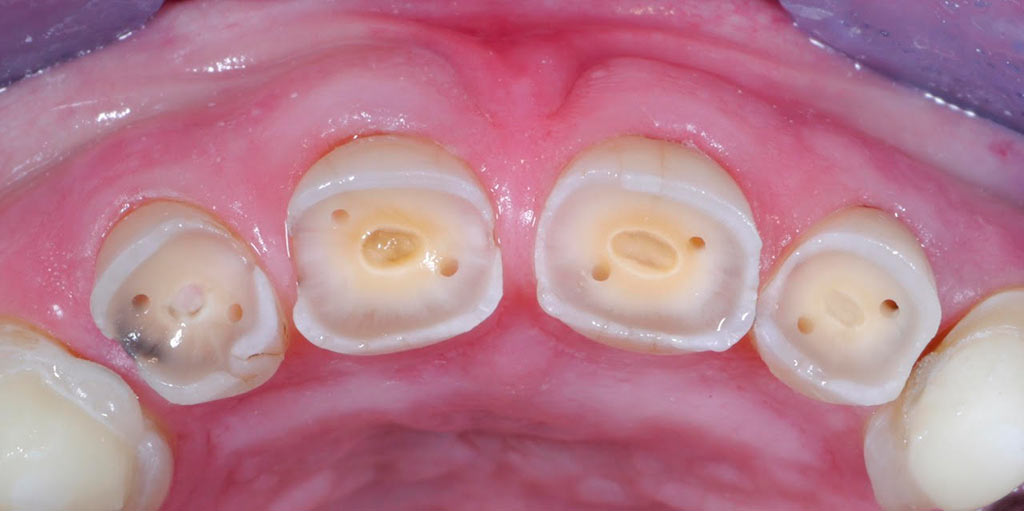

Rehabilitacion de paciente con destrucción dental